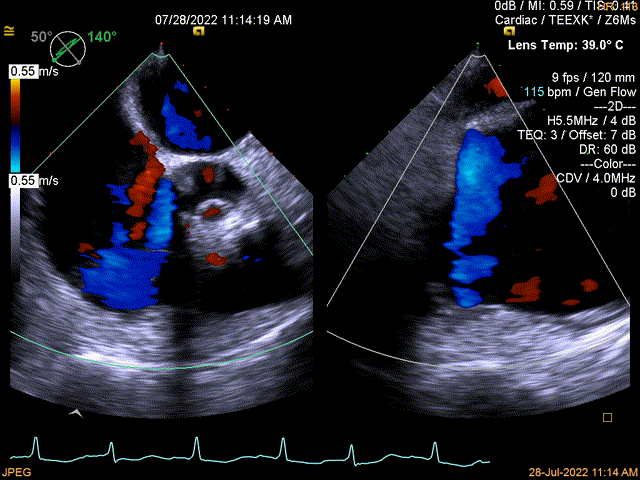

图2:术中TEE

同时其夹子系统继承于申淇淇麟®-经导管二尖瓣夹及可操控导引导管系统优秀设计,具备四个不同型号的夹子及瓣叶分开捕获能力,从而适用于更加复杂多变的三尖瓣解剖。因该患者三尖瓣反流束较宽,瓣叶存在较宽的关闭裂隙,术中很好的利用了瓣叶分开捕获的功能,于后隔瓣区域行瓣膜缘对缘修复。植入一枚长宽夹子后,术后即刻患者反流直接从5级减到2级,患者术后回复良好,自觉症状与临床病情明显改善。